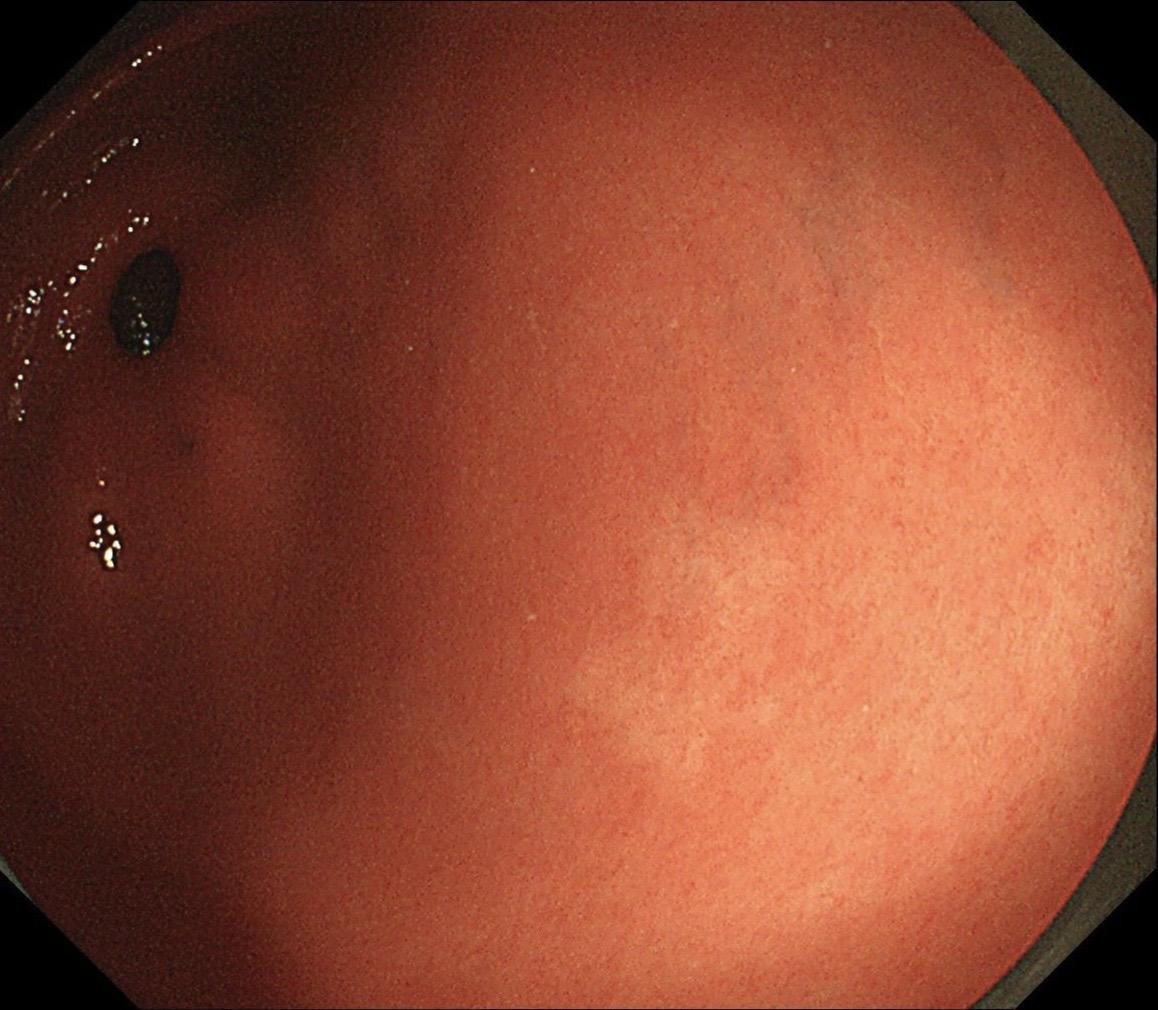

男,40岁,胃双发褪色调病变。慢性胃炎复查,3年前胃镜未见异常,Hp阳性背景,萎缩不明显,胃体下部大弯见一褪色调病变,浅凹陷,5mm左右,换用放大内镜观察,表面结构缺失,血管异型明显,未分化可能性大……胃窦后壁见一白斑,无高度差,NBI浅茶色,放大草草看了下,似有边界,IP增宽,活检待病理……小哥哥胖得几乎没脖子,腹式呼吸太明显~😖